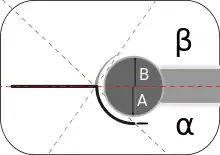

Imaging

Hip dysplasia can be diagnosed by ultrasound[42] and projectional radiography ("X-ray").[43] Ultrasound imaging is generally preferred at up to 4 months due to limited ossification of the femoral head up until then, and is the most accurate method for imaging of the hip during the first few months after birth. However, in most instances, ultrasound screening should not be performed before 3 to 4 weeks of age because of the normal physiologic laxity.[44][notes 1] When universal with targeted ultrasound screening was compared, the former results in an insignificant reduction in the late diagnosis of hip dysplasia, which is why universal ultrasonographic screening of newborn infants is not recommended by the American Academy of Pediatrics.[11]